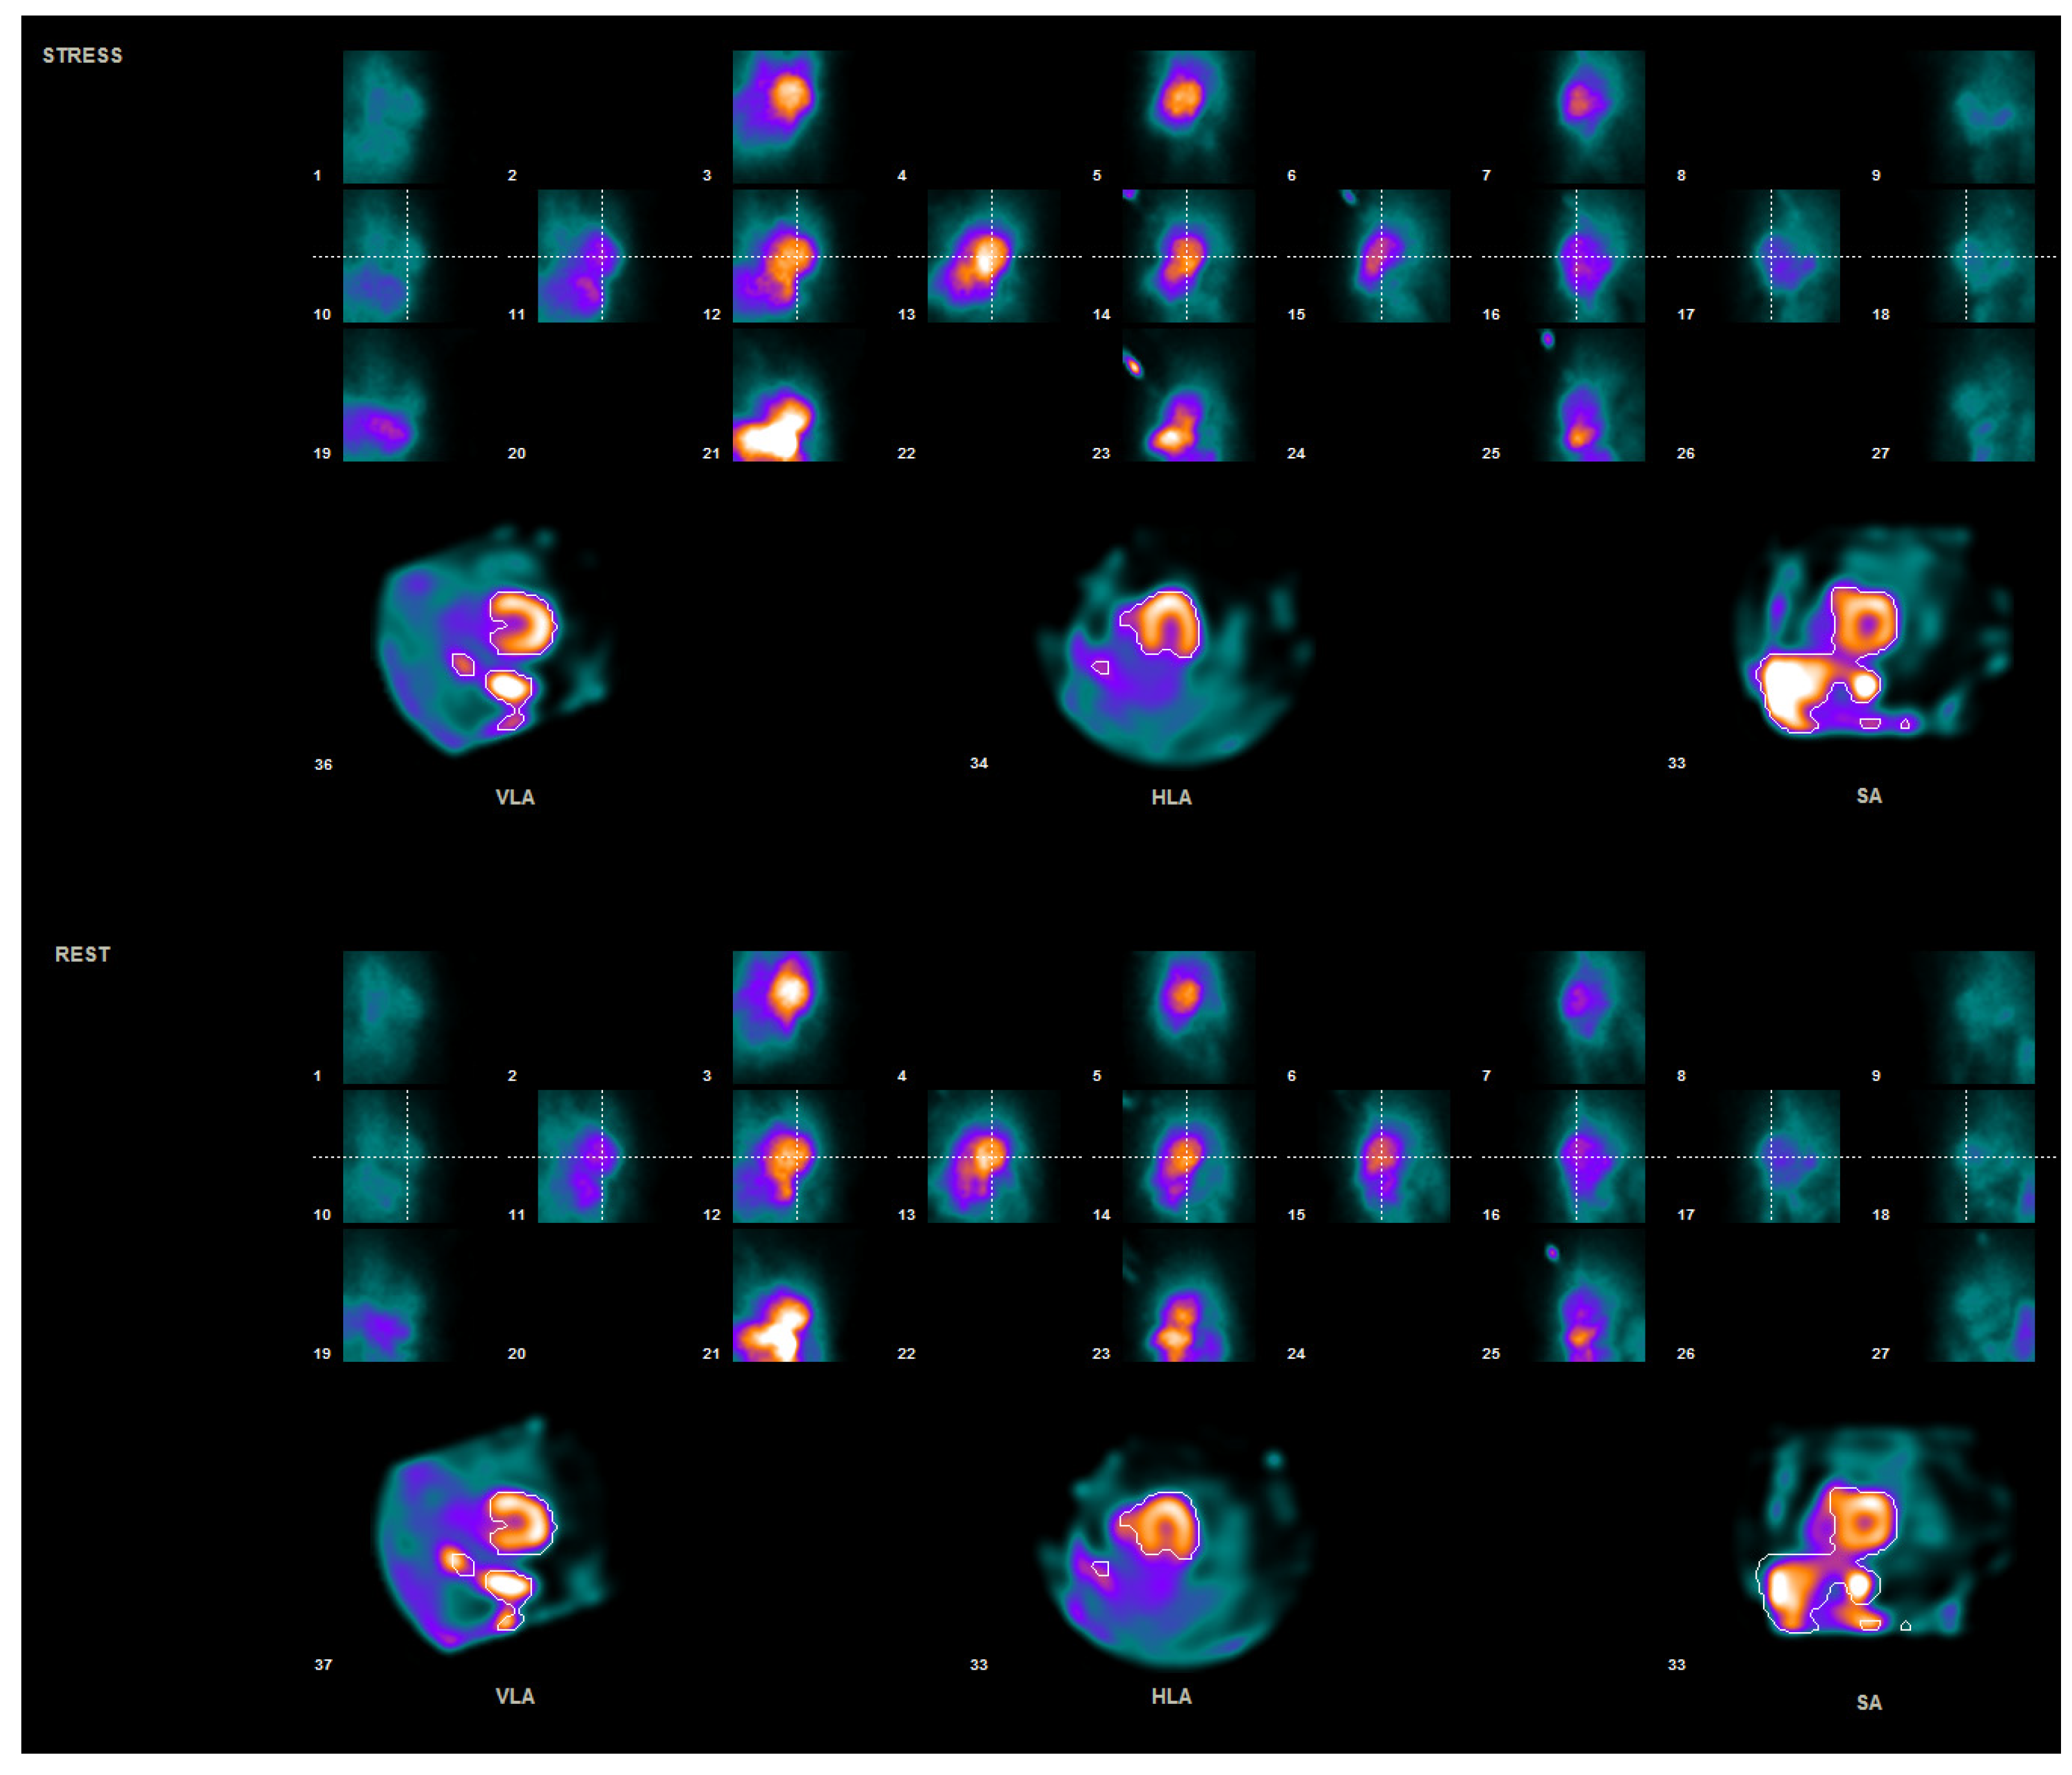

2. Materials and Methods

2.1. Patient Preparation and Data Acquisition

2.2. Data Processing